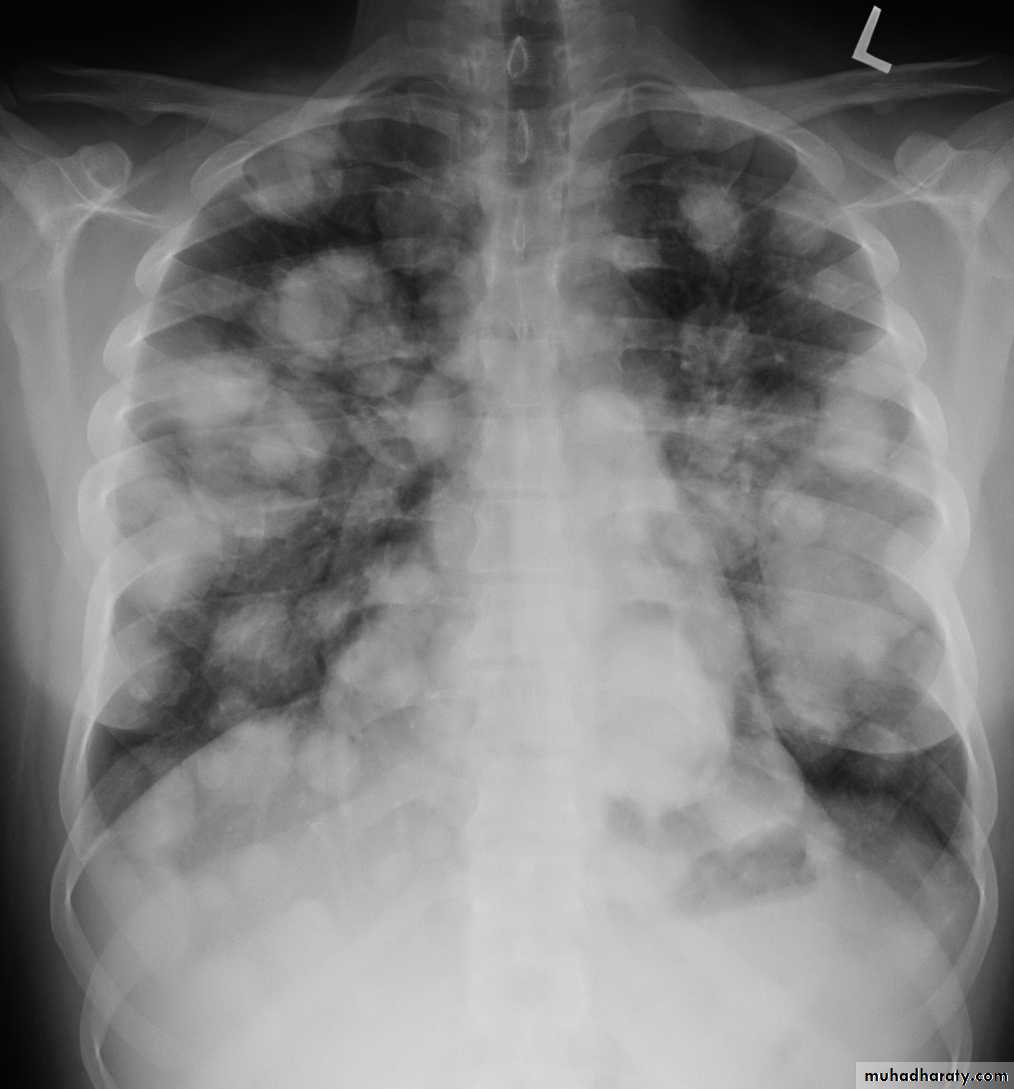

Pulmonary metastases are common and the result of metastatic spread to the lungs from a variety of tumors and can spread via blood or lymphatics.1.Cannonball metastases refer to large well circumscribed, round multiple opacities like cannonballs

2.lymphangitis carcinomatosis , is the term given to tumor spread through the lymphatics of the lung , and is most commonly seen secondary to adenocarcinoma Unfortunately up to a quarter of patients with subsequently established lymphangitic carcinomatosis have normal chest x-rays . When abnormal the most common finding is of a reticulonodular pattern, with thickening of the interlobular septae which may resemble Kerley B lines + /- pleural effusion .

3.innumerable small metastases (miliary pattern).